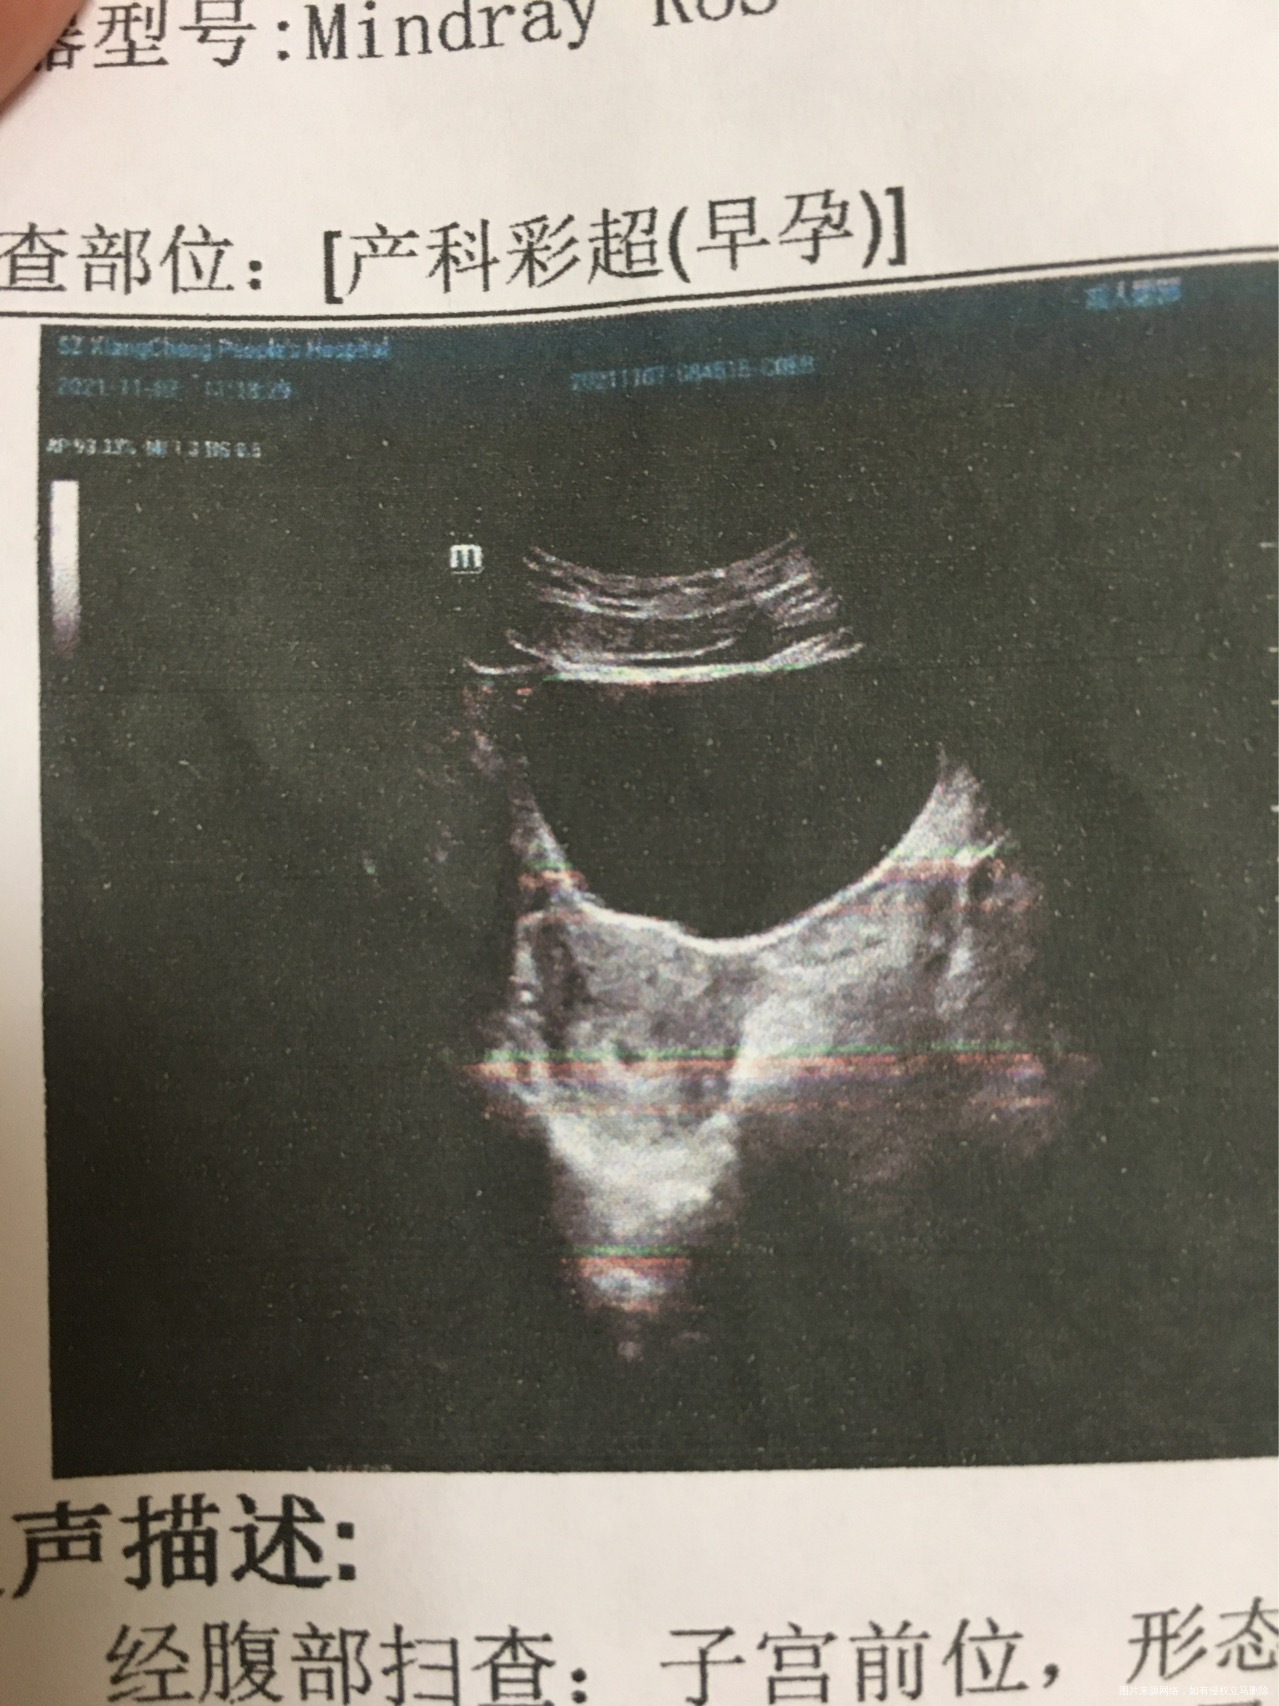

是怀孕了,宫内孕囊偏小的,孕酮值太低,如果打算要这个孩子建议用地屈孕酮和滋肾育胎丸保胎,10-14天后做B超看看胎芽胎心,放松心情祝你好孕,不能剧烈活动和同房。

只看到一个小孕囊,没有胎心和胎芽,不是很好,该用的药用上,注意休息,一周之后再去复查

血hcg和彩超提示怀孕35-38天左右,孕酮低,宫内孕,阴道流血,先兆流产,隔天查翻倍看看,建议服用地屈孕酮每次1片,每天2次保胎,禁同房,多休息。